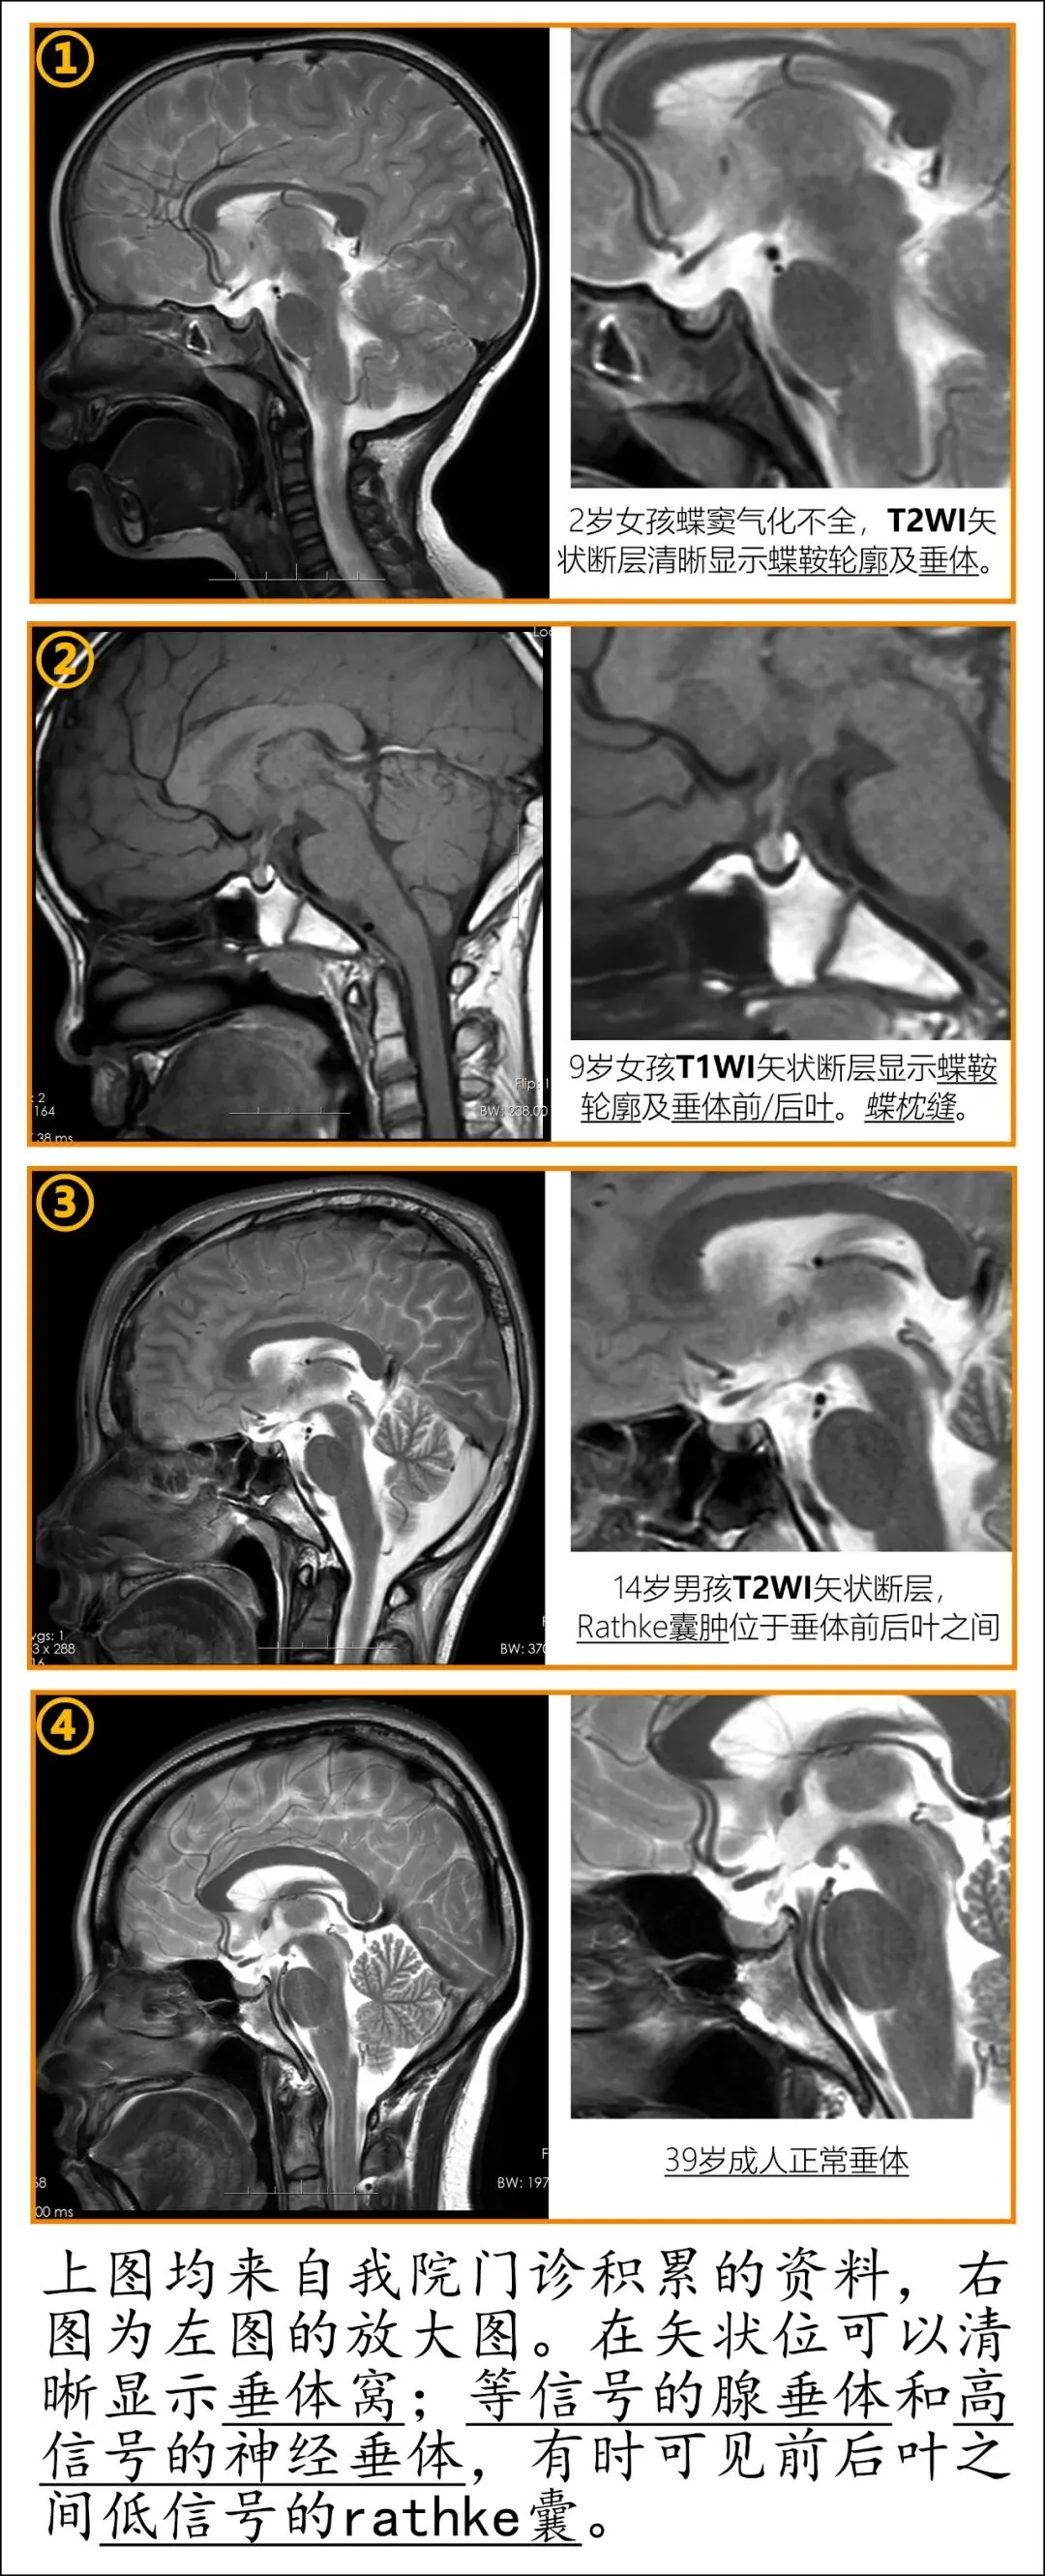

1. 矢状位

正中矢状位断层:可见视交叉、垂体柄、腺垂体、神经垂体、蝶鞍、蝶窦的关系。特别是儿童,蝶窦气化未完成,MR上可清晰可见蝶鞍的界限。